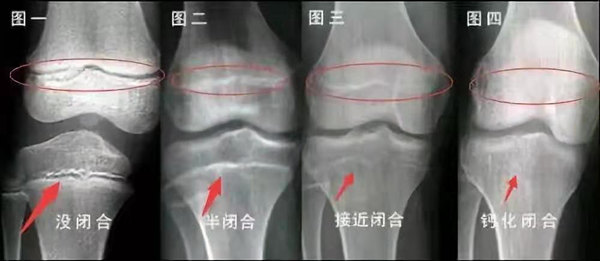

我們都知道,人體的高矮是由骨骼的生長發育決定的,特別是下肢長骨。長骨呈長管狀,在長骨的兩端有一種專管骨骼生長的骺軟骨,它與干骺端之間有一盤狀軟骨結構稱為骺板(線),在幼兒的X光片上表現為一條較寬的透光帶。 (見下圖)

未成年時隨著年齡的增加骺軟骨端不斷骨化,骨骼就不斷增長。當骨骺線完全閉合時骨骼就停止生長,個子也就不再增長了。一般骨骺端完全閉合的年齡是18~20歲左右。